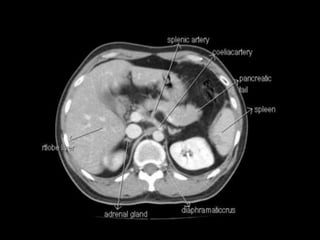

Retroperitoneum

The retroperitoneum is the part of the abdominal

cavity that lies between the posterior

parietal peritoneum and anterior to the transversalis

fascia.

It is divided into three spaces by the perirenal fascia and

is best visualised using CT or MRI.The three spaces are:

anterior pararenal space

perirenal space

posterior pararenal space

A fourth space, the great vessel space, is defined in the

recent literature

S = Suprarenal (adrenal) Glands

A = Aorta/IVC

D =Duodenum (except the

duodenal cap- first 2cm)

P = Pancreas (except the tail)

U = Ureters

C = Colon (ascending and

descending parts)

K = Kidneys

E = (O)esophagus

R = Rectum

Retroperitoneal organs